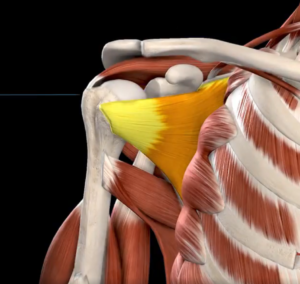

- Supraespinhal – responsável por iniciar a abdução do braço (levantar o braço lateralmente).

- Síndrome do Impacto (Impingement) – Ocorre quando os tendões do manguito rotador ficam comprimidos entre a cabeça do úmero e o acrômio, resultando em dor e inflamação. Se não tratada, essa condição pode levar a lesões mais graves.